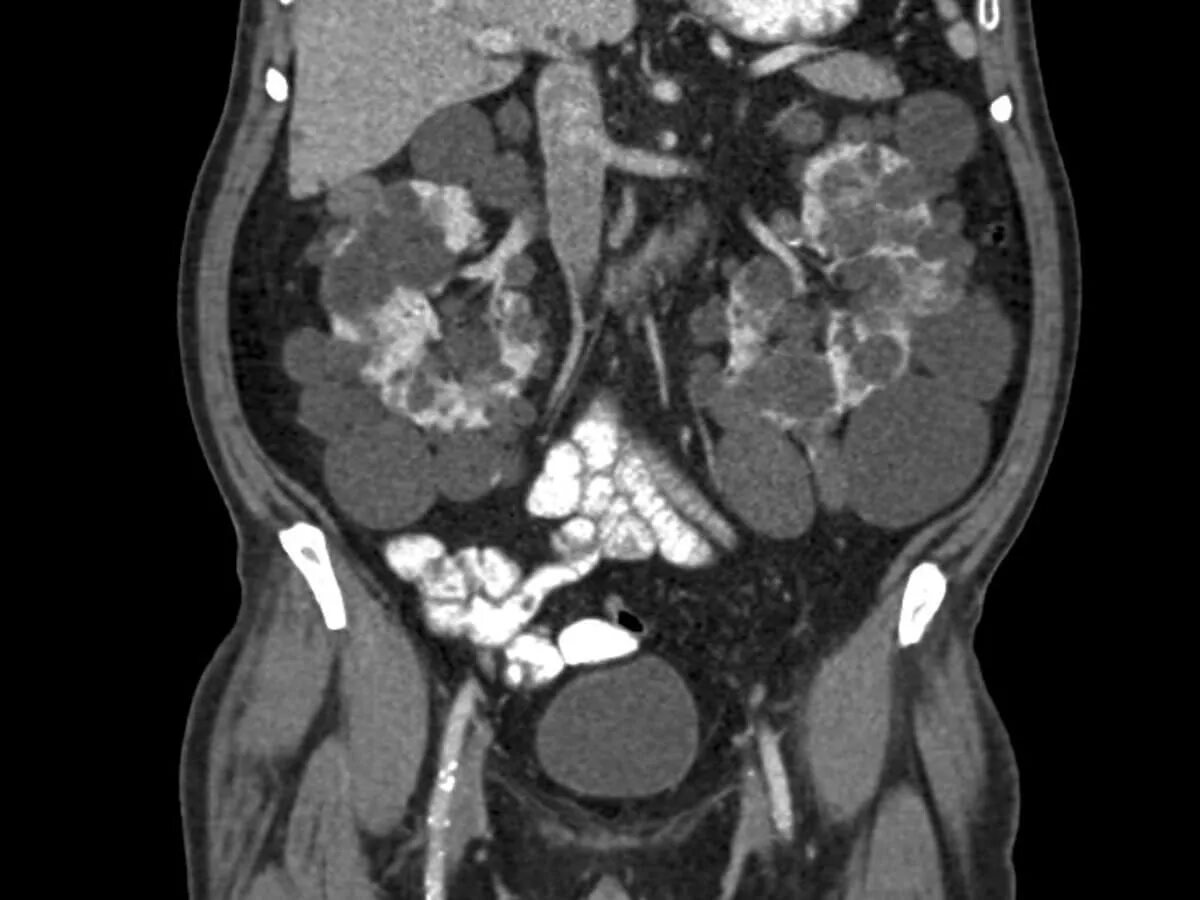

Ct search